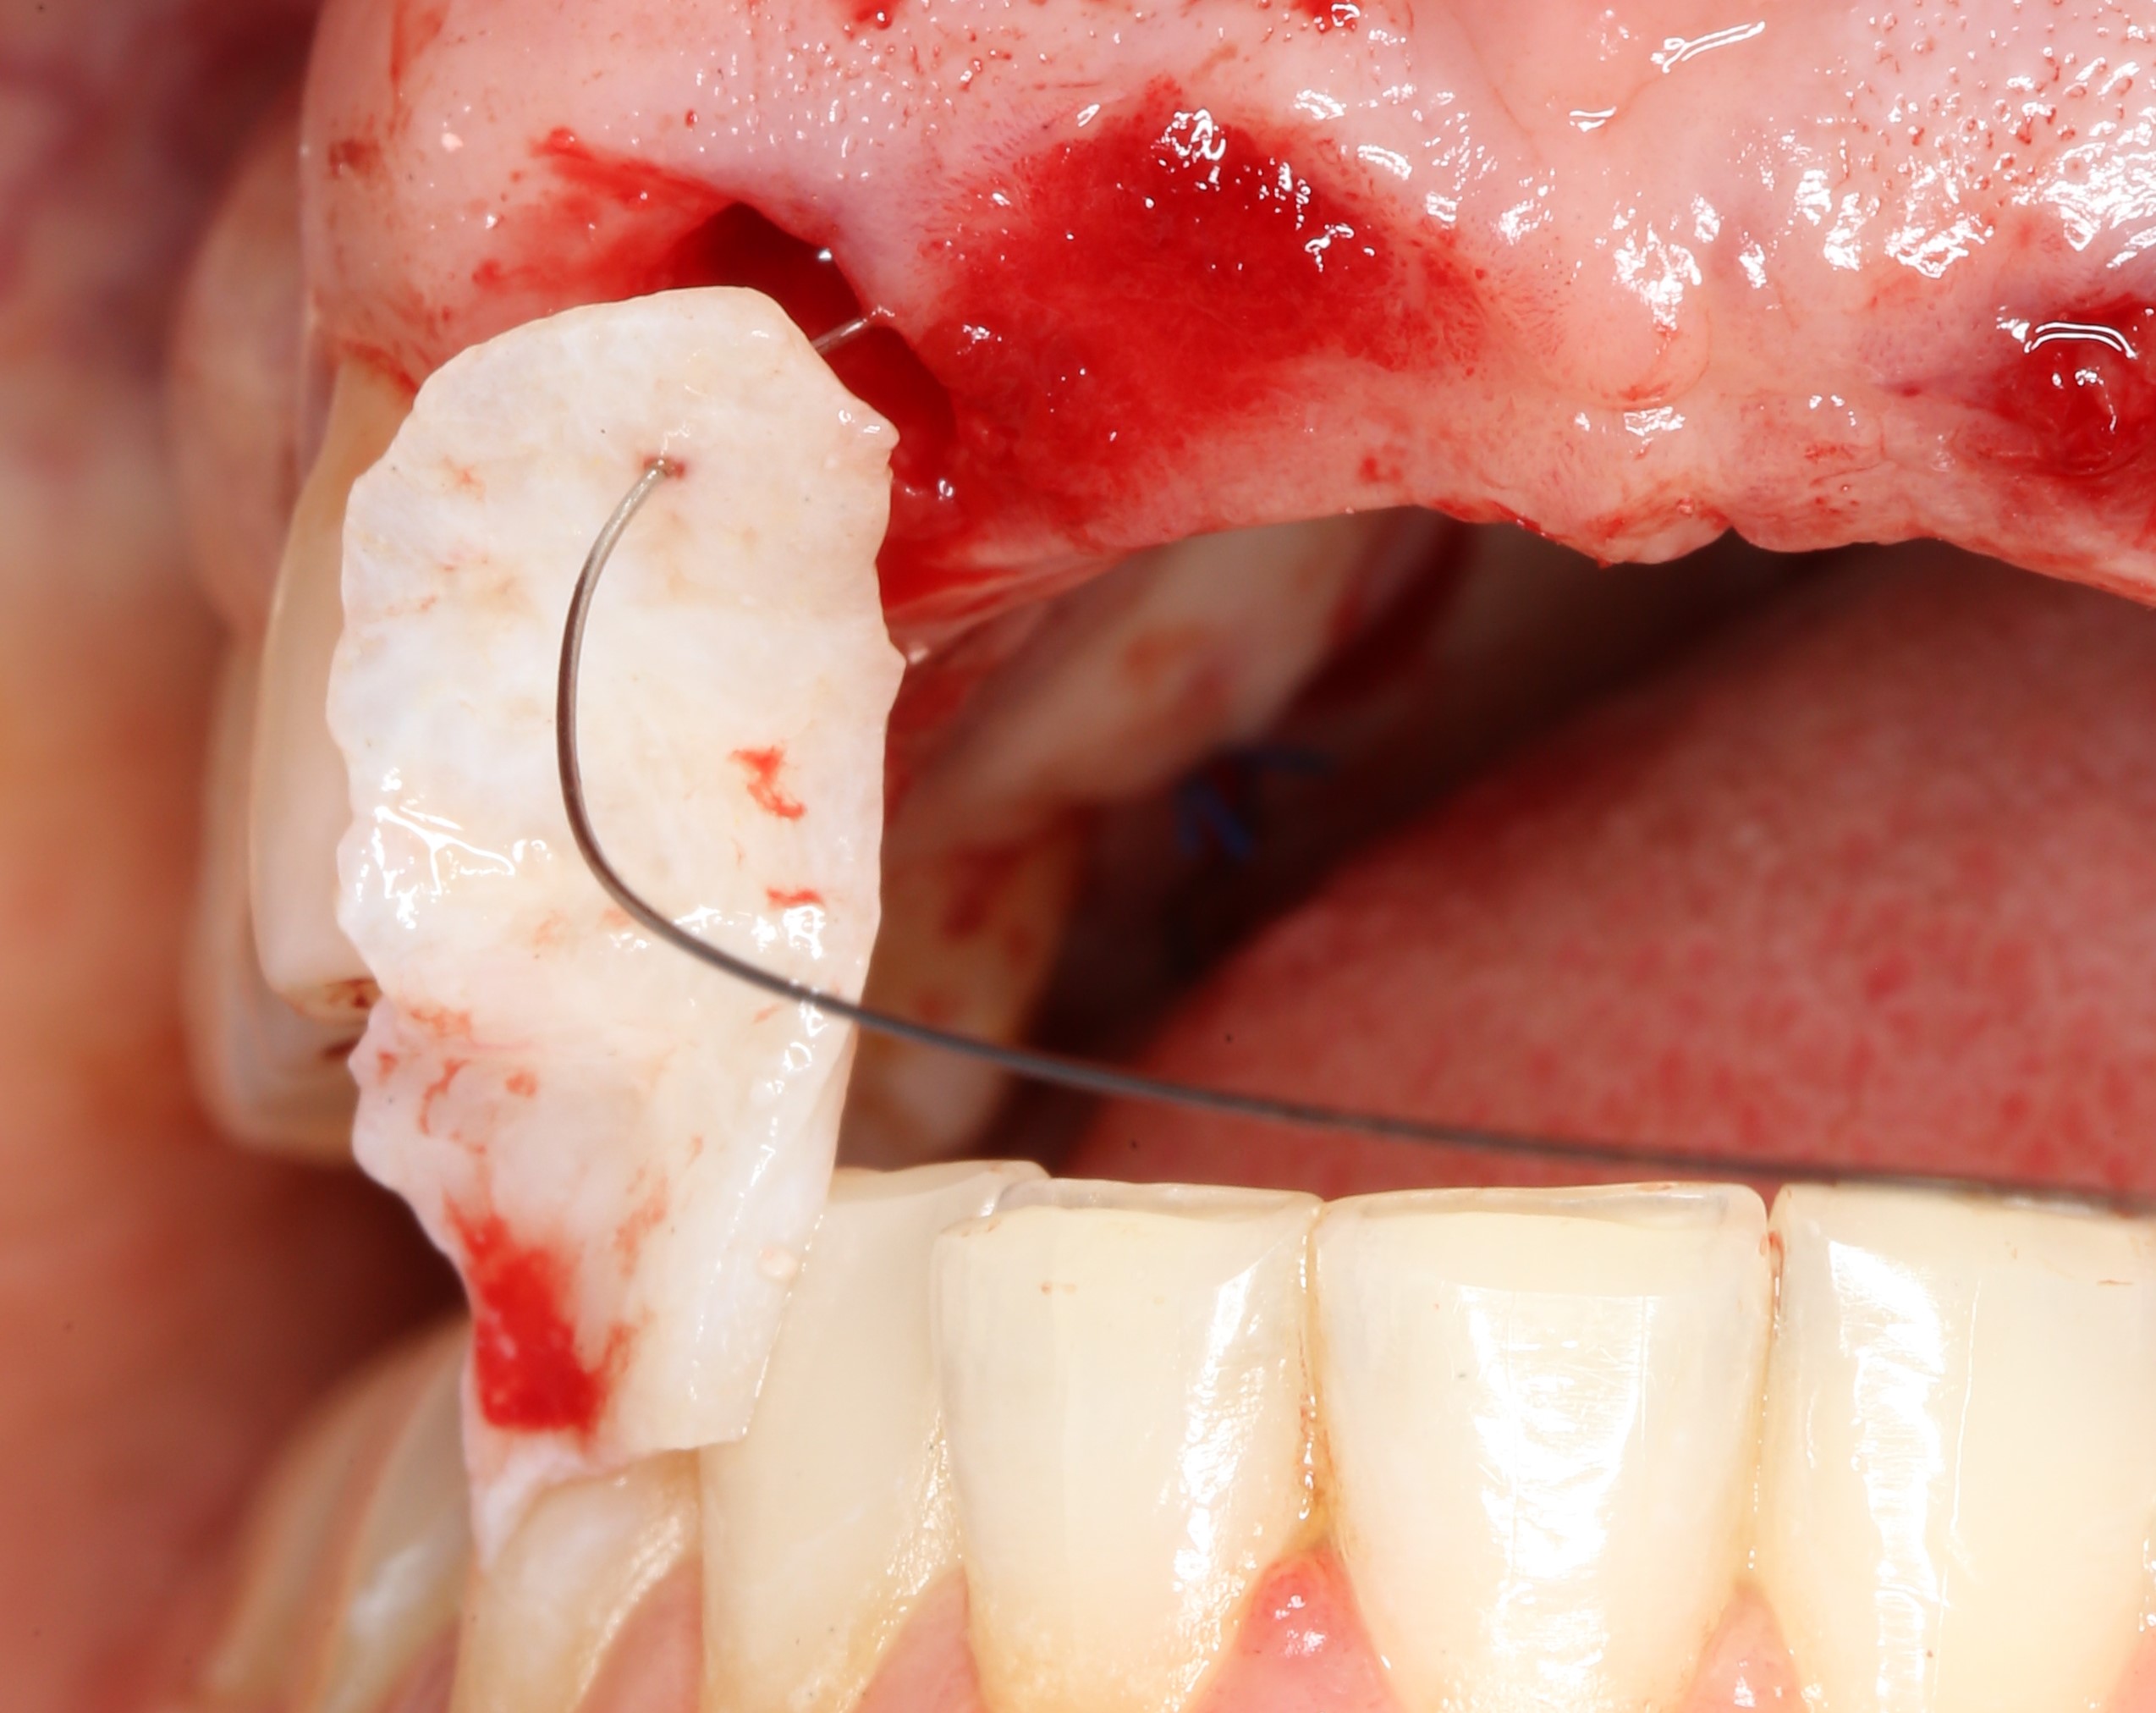

В качестве донорского участка мы выбираем отдел твёрдого нёба ближе к бугру верхней челюсти. Забор аутотрансплантата осуществляется методом расщепления:

При подходящих условиях и правильной реализации, это довольно комфортная для пациента методика получения аутотрансплантатов. При этом, они просты в обработке и почти деэпителизированы — нужно снять лишь тонкий слой эпителия «с торца» трансплантата:

Теперь нам нужно провести и зафиксировать его в тоннеле между лунками удалённых зубов. Для проводки мы решили использовать ортодонтическую проволоку. Как показала практика, это очень удобно и легко.